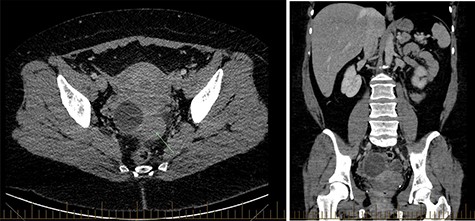

CT abdomen showed two cystic structures in the pelvis, and follow-up ultrasound demonstrated a 5.8-cm unilocular simple cyst contained within the right ovary, and a 3-cm left tubo-ovarian complex with associated hydrosalpinx (Figs 1–3).